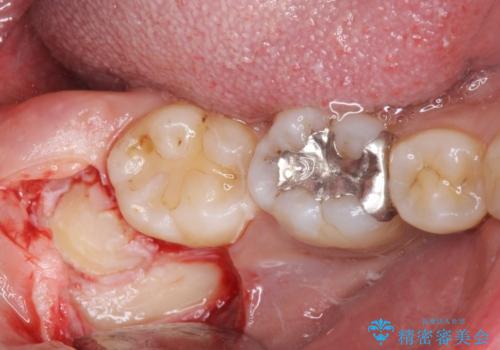

親知らず抜歯

- 親知らずの抜歯を希望された患者様です。

CTを撮り下顎の神経が近くない事を確認し抜歯を行いました。

親知らずの場所は磨きにくく、虫歯になるリスクが非常に高いです。

また親知らずの手前の歯の虫歯のリスクが高くなります。

なので虫歯になる前に抜歯をすることをお勧めします。